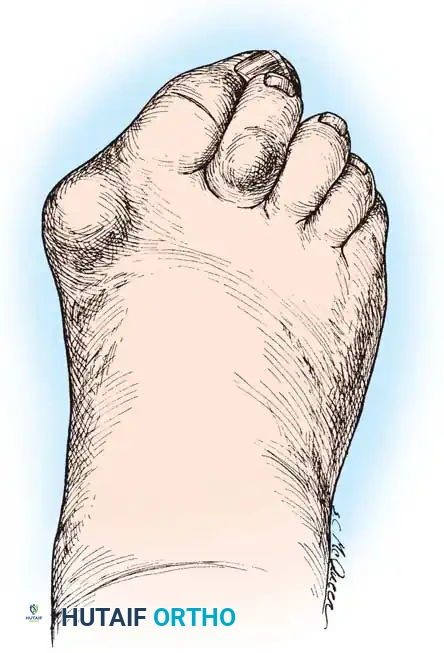

Hallux valgus (lateral deviation of the great toe) is not a single disorder, as the name implies, but a complex deformity of the fi rst ray that frequently is accompanied by deformity and symptoms in the lesser toes (Fig. 78-1). Often the angle between the fi rst and second metatarsals is more than the 8 to 9 degrees usually considered to be the upper limits of normal. The valgus angle of the fi rst metatarsophalangeal joint also is more than the 15 to 20 degrees considered to be the upper limits of normal (Fig. 78-2). If the valgus angle of the fi rst metatarsophalangeal joint exceeds 30 to 35 degrees, pronation of the great toe usually results. With this abnormal rotation, the abductor hallucis, which is normally plantar to the fl exion-extension axis of the fi rst metatarsophalangeal joint, moves further plantarward (Fig. 78-3). In this case, the only restraining medial structure is the medial capsular ligament with its capsulosesamoid portion (inserting into the base of the proximal phalanx) (Fig. 78-4) and capsulophalangeal portion (inserting into the plantar plate). The adductor hallucis, which is unopposed by the abductor hallucis, pulls the great toe further into valgus, stretching the medial capsular ligament (particularly the capsulosesamoid), attenuating this structure, and allowing the metatarsal head to drift medially from the sesamoids. In addition, the fl exor hallucis brevis, fl exor hallucis longus, adductor hallucis, and extensor hallucis longus increase the valgus moment at the metatarsophalangeal joint, further deforming the fi rst ray. The deep transverse intermetatarsal ligament runs between the plantar plates at the metatarsophalangeal joints and does not insert into bone on the adjacent sides of the metatarsal heads. Finally, the sesamoid ridge on the plantar surface of the fi rst metatarsal head (the crista) fl attens because of pressure (abutment) from the tibial sesamoid (Fig. 78-5). With this restraint lost, the fi bular sesamoid displaces partially or completely into the fi rst intermetatarsal space (see Fig. 78-2). In this situation, the patient is bearing less weight on the fi rst ray and more on the lesser metatarsal heads, increasing the likelihood of transfer metatarsalgia, callosities, and stress fracture of a lesser metatarsal.

Fig. 78-1 Multiple components of hallux valgus and associated deformities.

a congruent metatarsophalangeal articulation; phalangeal osteotomy or distal metatarsal osteotomy, rather than tightening of the medial capsular repair, should be used for further correction. The valgus posture of the great toe frequently causes a hammer toe–like deformity of the second toe (Fig. 78-7). In addition, the splaying of the forefoot makes the wearing of shoes more diffi cult; with shoes that have a narrow toe box, corns often develop, as does bursal hypertrophy over the medial eminence of the fi rst metatarsal head (bunion). With valgus subluxation of the fi rst metatarsophalangeal joint, osteoarthritis frequently develops. In this case, the entire spectrum of hallux valgus is present: varus deformity of the fi rst metatarsal, valgus of the great toe, bunion formation, arthritis of the fi rst metatarsophalangeal joint, hammer toe of one or more toes, corns, calluses, and meta-